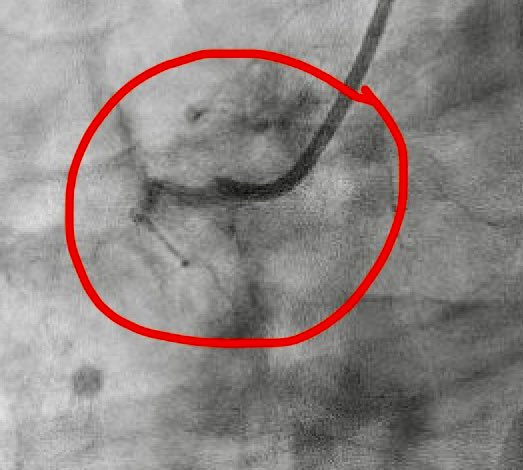

2/2 large RCA-RA /CS fistula. AO 90/63 PA 53/15. O2% RA 61 PA 65 AO 96. How do you explain RA sat( I expected 80s) and normal RV size? @ramymandoMD @IvanHansonMD @amrabbasmd @BeaumontIC @BeaumontCards @Babar_Basir @CMichaelGibson @NalassaadNihad @ANbilolikar

@yasirjawaid888 @ekgpdx @RajTayal2 @heartdoc45 @DrAmirKaki @HadyLichaaMD @DrJayMohan @chadialraies @BaoGTran @AKassier @raatassi @ShariqShamimMD @trivaxheartmd It’s 5f JR4 at RA/ CS junction

You may not have shunt detected in coronary RA fistula due to dilution of minimal coronary flow compared to systemic flow and unless you sample at the mouth of fistula. If PA sat is normal, then there is no shunt, if elevated, then fistula mouth in RA wasn’t sampled.

@amrabbasmd @ramymandoMD @IvanHansonMD @BeaumontIC @BeaumontCards @Babar_Basir @CMichaelGibson @NalassaadNihad @ANbilolikar Oh that makes sense. The sampling was at the CS/ RA junction not exactly at the month of the fistula. What you’re saying about coronary flow makes sense but it’s just hard to imagine that that big of a fistula does not cause much shunting

@HoumanKhalili @Wisam_Alhumam @ramymandoMD @IvanHansonMD @amrabbasmd @BeaumontIC @BeaumontCards @Babar_Basir @CMichaelGibson @NalassaadNihad @ANbilolikar Mid RA was 61 SVC 62. Repeated and rechecked twice

@Wisam_Alhumam @ramymandoMD @IvanHansonMD @amrabbasmd @BeaumontIC @BeaumontCards @Babar_Basir @CMichaelGibson @NalassaadNihad @ANbilolikar It did not detect a shunt

@raatassi @ramymandoMD @IvanHansonMD @amrabbasmd @BeaumontIC @BeaumontCards @Babar_Basir @CMichaelGibson @NalassaadNihad @ANbilolikar Planning CTA as OP to better understand. I’m still puzzled by the lack of high RA sat and significant RV dilation with the amount of “ contrast shunt”

@raatassi @ramymandoMD @IvanHansonMD @amrabbasmd @BeaumontIC @BeaumontCards @Babar_Basir @CMichaelGibson @NalassaadNihad @ANbilolikar Yes I put a swan from R Fem. When RA sat didn’t make sense to me I put a wire to prove the connection RCA- RA is real.

@LuaySayed @ramymandoMD @IvanHansonMD @amrabbasmd @BeaumontIC @BeaumontCards @Babar_Basir @CMichaelGibson @NalassaadNihad @ANbilolikar Is it rca - cs- ra?